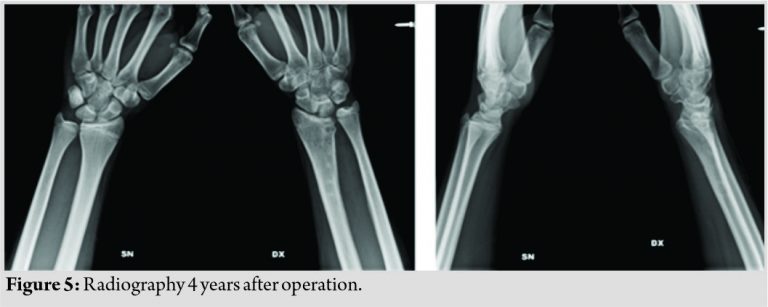

Post-operative radiography, taken at 5 weeks, showed consolidation of the osteotomy. During the follow-up, the continuity of the open physis and the progressive lengthening of the right distal radius was documented by X-rays (Fig.3). The plate and screws were removed at 12 months. At follow-up, 4 years after surgery, the range of movement in both wrists was symmetrical (Fig. 4).

Radiographs showed a satisfactory alignment of distal radius (Fig. 5).